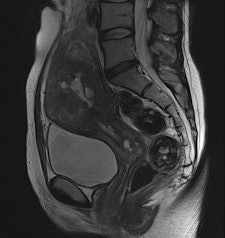

They found BLADE significantly (p < 0.0001) reduced motion and ghosting artifacts and showed improved conspicuity, but overall image quality did not differ significantly in the 47 patients who underwent sagittal BLADE and conventional TSE at 1.5-tesla after glucagon administration. In the majority of cases (53.2% versus 59.6%), radiologists preferred conventional TSE due to better image contrast and visibility of free pelvic fluid. Signal-to-noise ratio (SNR) and contrast-to-noise ratio (CNR) were significantly higher on conventional TSE.

"Indeed, conventional T2-weighted TSE provided a significantly better visibility of free pelvic fluid or cystic structures (i.e., a relatively higher effective T2 weighting) in numerous cases," the researchers noted.

BLADE improves anatomic depiction and image quality thanks to less movement artifact, but at the expense of CNR of cystic structures or visibility of free pelvic fluid.